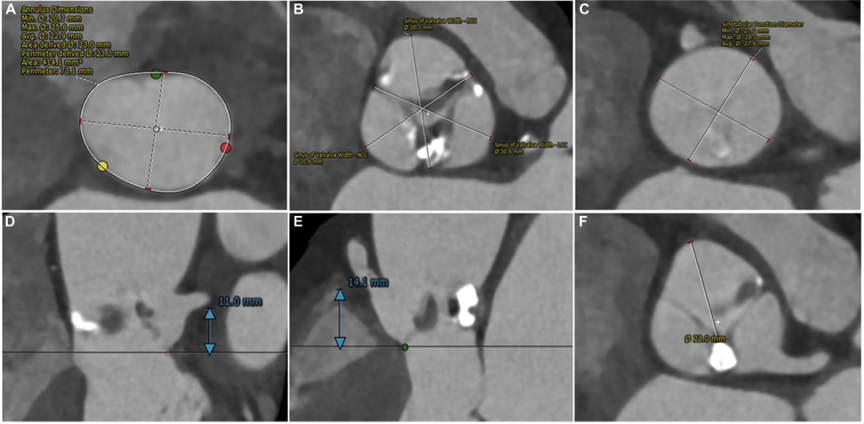

MDCT的进一步解剖测量包括73.1 mm的环形周长、414.1 mm2的环形面积、11 mm的左主冠状动脉(LMA)开口高度和14.1 mm右冠状动脉(RCA)(图1A、B、D、E)。左、右和非冠状窦的尺寸分别为31.6、30.7和30.7 mm(图1B)。窦房结的平均尺寸和高度分别为27.6和16 mm(图1C)。在右冠状动脉口平面上测量,钙化结节边缘到右冠状动脉开口的距离为23 mm(图1F)。右股动脉、髂外动脉和髂总动脉的平均内径分别为6.7、6.5和7.3mm。该患者被认为处于中等手术风险,胸外科医师学会评分为5.13%,建议进行外科主动脉瓣置换术(SAVR)。然而,患者拒绝接受SAVR,并决定接受微创TAVR。

图1. 主动脉根部的术前计算机断层扫描评估